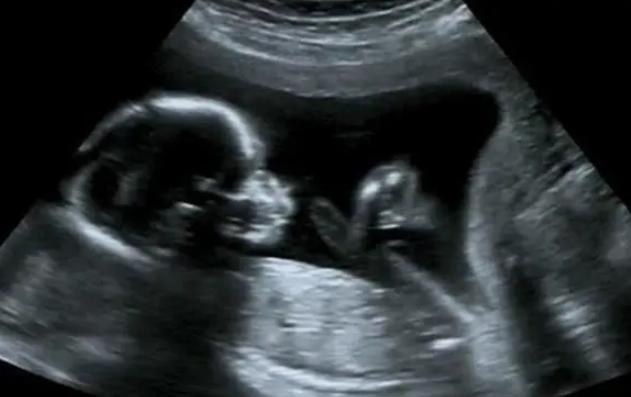

而B超检查主要是以黑白B超为主,它所显现出来的结果就像普通照相机的黑白照片一样,她也能够显示人体子宫的情况,尤其是孕妇在检查时会显示出血管的信息,相对来说,检查的范围会比较低一些。

一般来说,彩超主要是在高清晰度的黑白B超上加上彩色多普勒对血流的检查,彩超相对来说分辨率比较高一些,而且它所检查的范围也会比较广泛一些,在进行检查的时候通过彩超检查能够更加直观的知道所要检查的部位的情况,不过相对来说,彩超检查所使用的费用要比黑白B超的高一些。

彩超和黑白B超主要的区别是在于血流所呈现出来的清晰度以及所检查的费用,如果是经济允许的情况下,可以选择彩超检查。另外需要知道的是如果是孕妇在孕早期,就尽量不要进行彩超检查,因为彩超检查所带来的超声波影响会比B超要大得多,因此在孕早期比较好进行黑白B超。

小提示:b超彩超区别在哪,孕妇选择哪种更合适,B超检查的范围比较小,提供的信息有限制,而彩照检查范围比较广,更加的清晰,两者各有利弊,大家可以根据自身情况参考医生意见进行选择。